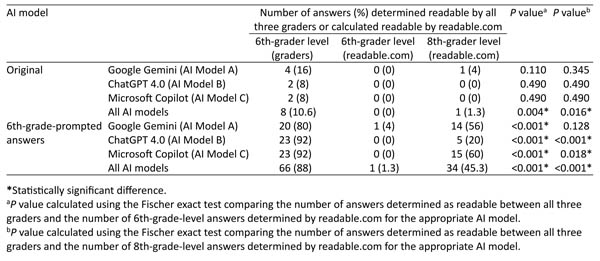

Evaluation of artificial language-adjusted readability on cataract surgery queries